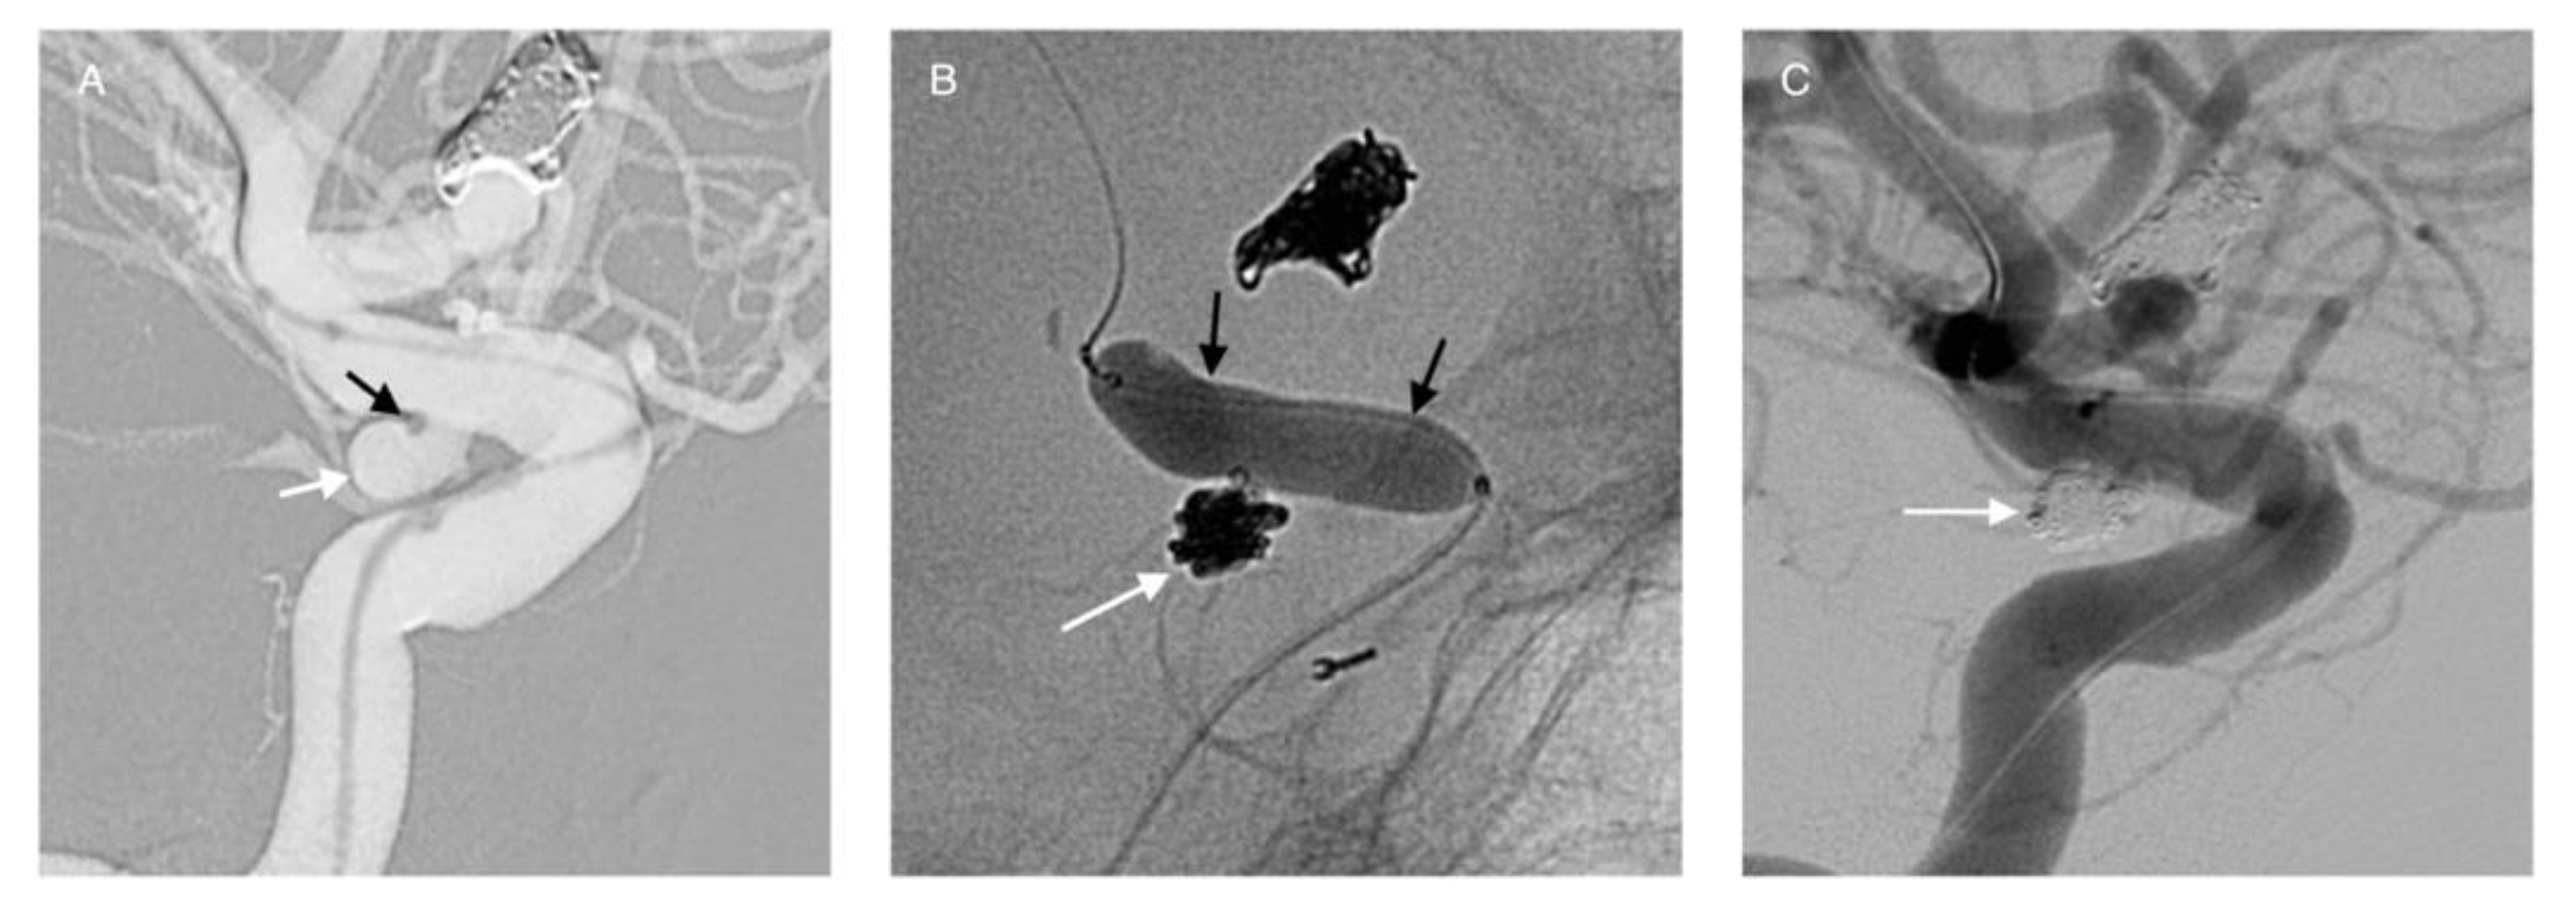

3.2. Balloon-Assisted Coiling (BAC)